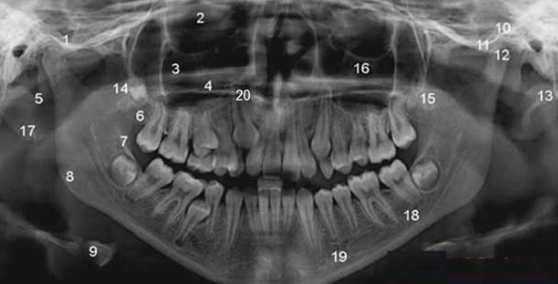

파노라마 방사선 사진이나

치주낭 깊이 측정 등을 통해

현재 잇몸 상태를 정확히

파악하는 것이 중요합니다.